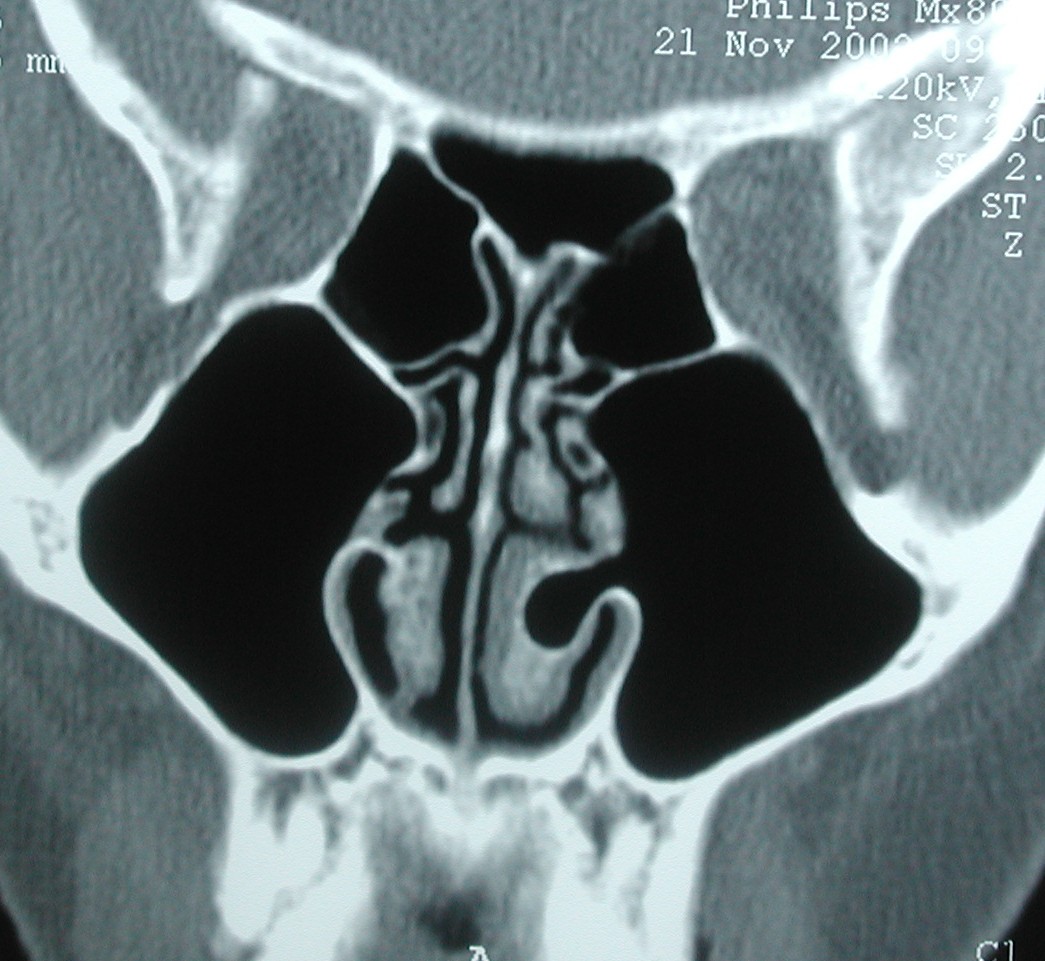

This patient has a fascinating finding: a concha bullosa of the inferior turbinate.  It is hard to explain how this occurred embryologically, as the IT is a separate bone from the maxilla containing the sinus.e